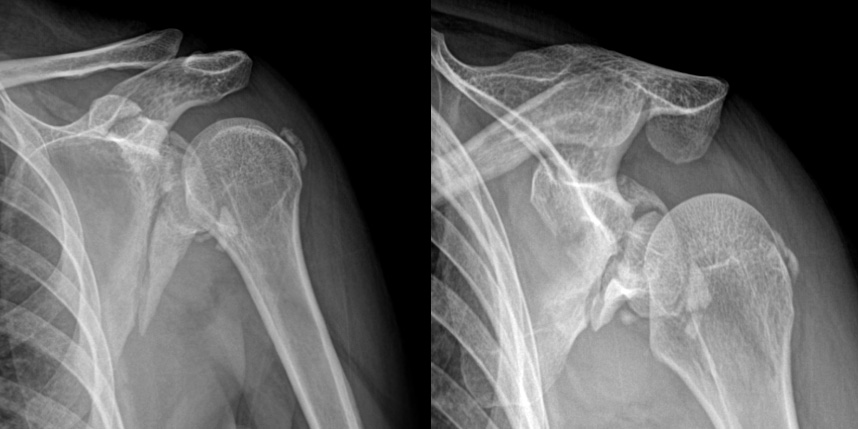

골절은 정확하게 골절편을 잘 맞추고 고정하는 것이 중요합니다. 특히 관절면을 잘 맞추는 것이 중요합니다.

상완골 골절